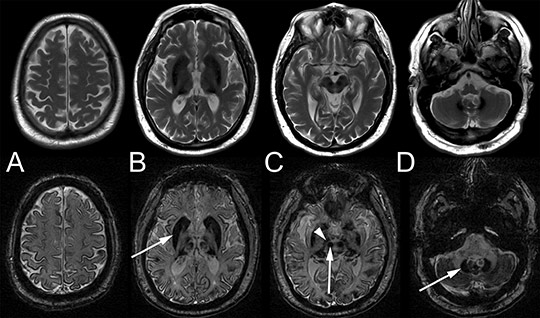

Neurological examination revealed unsteady gait, ataxia in the knee-heel test, abnormal performance in the finger-nose test, intention tremor and slow saccades, which could indicate cerebellar disease. MRI of the head revealed widespread iron deposits in the cerebral cortex, brainstem nuclei and basal ganglia (Fig. 1), but not in the meninges. Cerebrospinal fluid was normal, apart from slightly elevated total protein. Examination of dementia markers revealed a non-specific increase in tau protein and normal β-amyloid.

Figure 1  Cerebral MRI of the patient in his late 50s. T2-weighted (upper row) and susceptibility-weighted (SWI, bottom row)…

Figure 1 Cerebral MRI of the patient in his late 50s. T2-weighted (upper row) and susceptibility-weighted (SWI, bottom row) series. SWI is significantly more sensitive to iron deposition than the T2 series. There is widespread and symmetrical iron deposition, with deposits revealed by hypointensities in the cerebral (A) and cerebellar cortex (D), striatum (arrow in B), red nucleus and substantia nigra (arrow and arrowhead in C) and the dentate nucleus of the cerebellum (arrow in D)

The patient had iron deposition centrally in the brain, with progressive neurological symptoms and pathology in several areas of the central nervous system, including the retina. This combination of neurological symptoms plus iron accumulation in the brain and other organs is seen in a number of distinct progressive conditions known as «neurodegeneration with brain iron accumulation» (NBIA) (6, 7). In these disorders, the accumulation of iron in the brain, particularly in the basal ganglia, can most easily be seen in T2-weighted and susceptibility-weighted MR images (SWI).